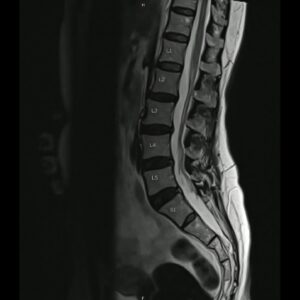

また、近年のパンデミックがもたらした新たな知見として、COVID-19の後遺症に伴う頭痛の研究(Lancet Neurol 2022年)があります。この研究では、ウイルス感染による血栓性二次頭痛の増加が報告されており、MRV(磁気共鳴静脈造影)による血管評価の重要性が再認識されました。動脈解離におけるMRIの「pearl and string sign(真珠と紐のような像)」など、画像診断技術の進化は、かつて見逃されていた微細な血管異常の特定を可能にしています。しかし一方で、米国における頭痛画像の約30%が不適切、つまり医学的に不要な検査であったという指摘もあり、画像診断の適正化と被曝リスクの管理は、医療経済学的な観点からも議論の的となっています。